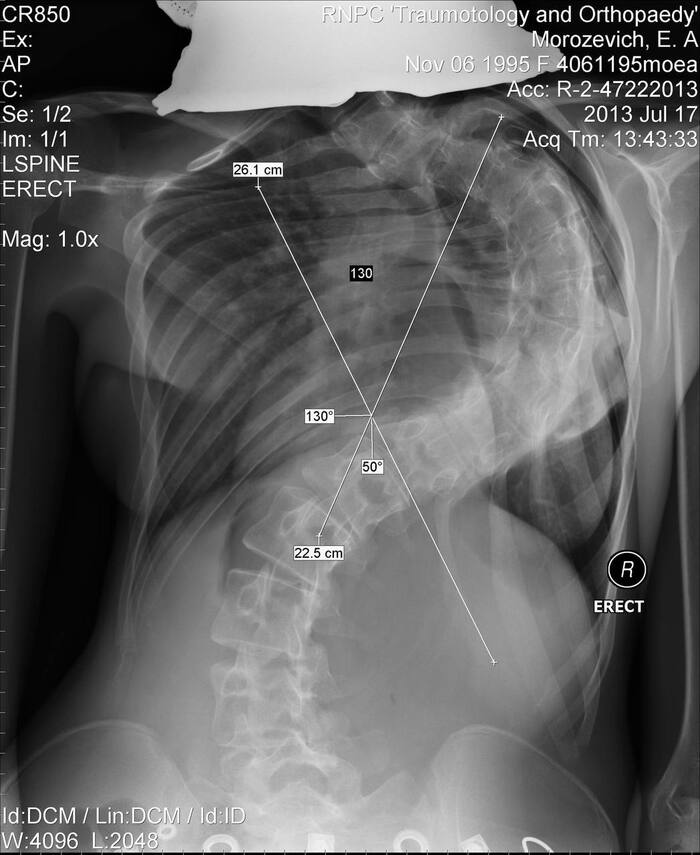

В июле 2013 года искривление составляло уже 132 градуса. Мне было 17 лет, я училась в 11 классе.

Я была очень худой, кривой, а когда шла, то была отдышка. Кто-то спрашивал в комментариях под другим постом, как ко мне относились сверстники, не обижали ли меня, не обзывались ли. Отвечаю, что нет, такого не было никогда. У меня всегда было много хороших и отзывчивых друзей :)

В ноябре 2013 года мне исполнилось 18 лет, я очень ждала операции и была к ней готова. Госпитализация и операция была назначена на февраль 2014 года в РНЦП Травматологии и ортопедии г. Минска, кстати там же я всё время и наблюдалась.

К моменту госпитализации искривление составляло уже 140-150 градусов, точно не помню. Вес был 36 кг, рост 156.